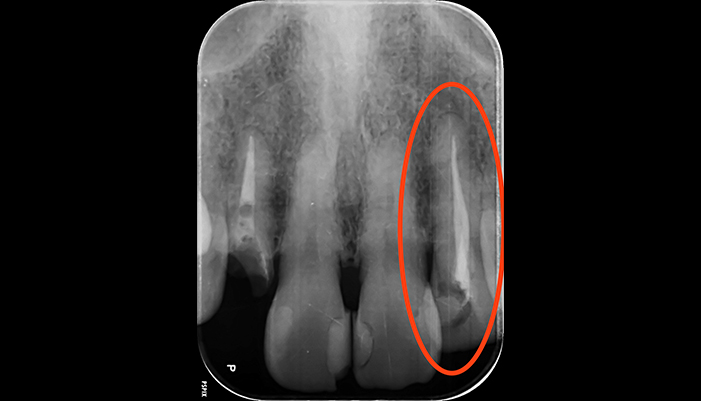

治療前

治療後

| 主訴 | 歯茎が腫れている |

|---|---|

| 治療期間 | 2回 |

| 費用 | 再根管治療154,000円(税込)+ ファイバーコア44,000円(税込)= 198,000円(税込) |

| 治療内容 |

ラバーダムを用いて無菌的な環境下で根管治療を行いました。 マイクロスコープ下で虫歯を完全に取り切り、NiTiファイルを用いた根管形成、薬液や超音波器具による洗浄、その後根管内をさらに消毒するため水酸化カルシウムを入れて仮の蓋をしました。 2回目は体に馴染みの良い材質による充填、被せ物を支え、再感染しないように土台を立てました。 |